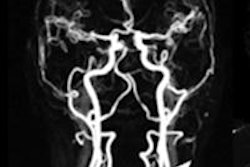

Not every modality is adequate for assessing the presence of atherosclerosis in asymptomatic individuals, but MRA is a good candidate owing to its lack of ionizing radiation, noninvasive nature, and lower toxicity vis-à-vis CT angiography (CTA) with iodinated contrast. And previous studies have shown that MRA has high sensitivity and specificity for gauging the extent of atherosclerosis in patients with vascular disease compared with digital subtraction angiography as the gold standard.

Contrast-enhanced MR angiography was performed using parallel techniques for spatial resolution less than 1.5 mm3 for classification of mild stenosis (≤ 50% luminal narrowing), moderate stenosis (50% to 70%), or high-grade stenosis (≥ 70%). Two highly experienced radiologists evaluated the data individually, discussing and recording their findings in consensus.

A total of 26.8% of participants showed pathological changes in at least one vessel segment. Atherosclerosis was found in 18 (7.2%) of patients, and atherosclerotic changes were found in one vascular territory in 39 subjects. An additional 25 subjects (18.1%) had stenosis in a second arterial segment, and as many as five arterial vascular regions were affected in two cases (1.4%).

Fully 7.2% of the subjects showed mild to moderate luminal narrowing in at least one vascular territory, and another 5.8% had at least one stenosis of 50% or more. Meanwhile, 86.9% of individuals presented without any stenoses.

In the carotid arteries, stenoses were detected in seven individuals (4.9%), including four mild and two moderate cases. In one case, the researchers found a high-grade stenosis of the proximal carotid artery.

Aortic plaques were found in six cases, while iliac artery plaques were seen in four cases that lacked luminal narrowing. In all, there were 10 mild stenoses, seven medium-graded stenoses, and seven high-grade stenoses within the large arterial vessels, as well as two low-grade aortic aneurysms. In the kidneys, the group found one mild stenosis and one case of plaque without luminal narrowing.

The most commonly detected atherosclerotic abnormalities were in the lower leg, with 12 individuals presenting with mild (n = 2), moderate (n = 3), or severe (n = 7) stenosis.